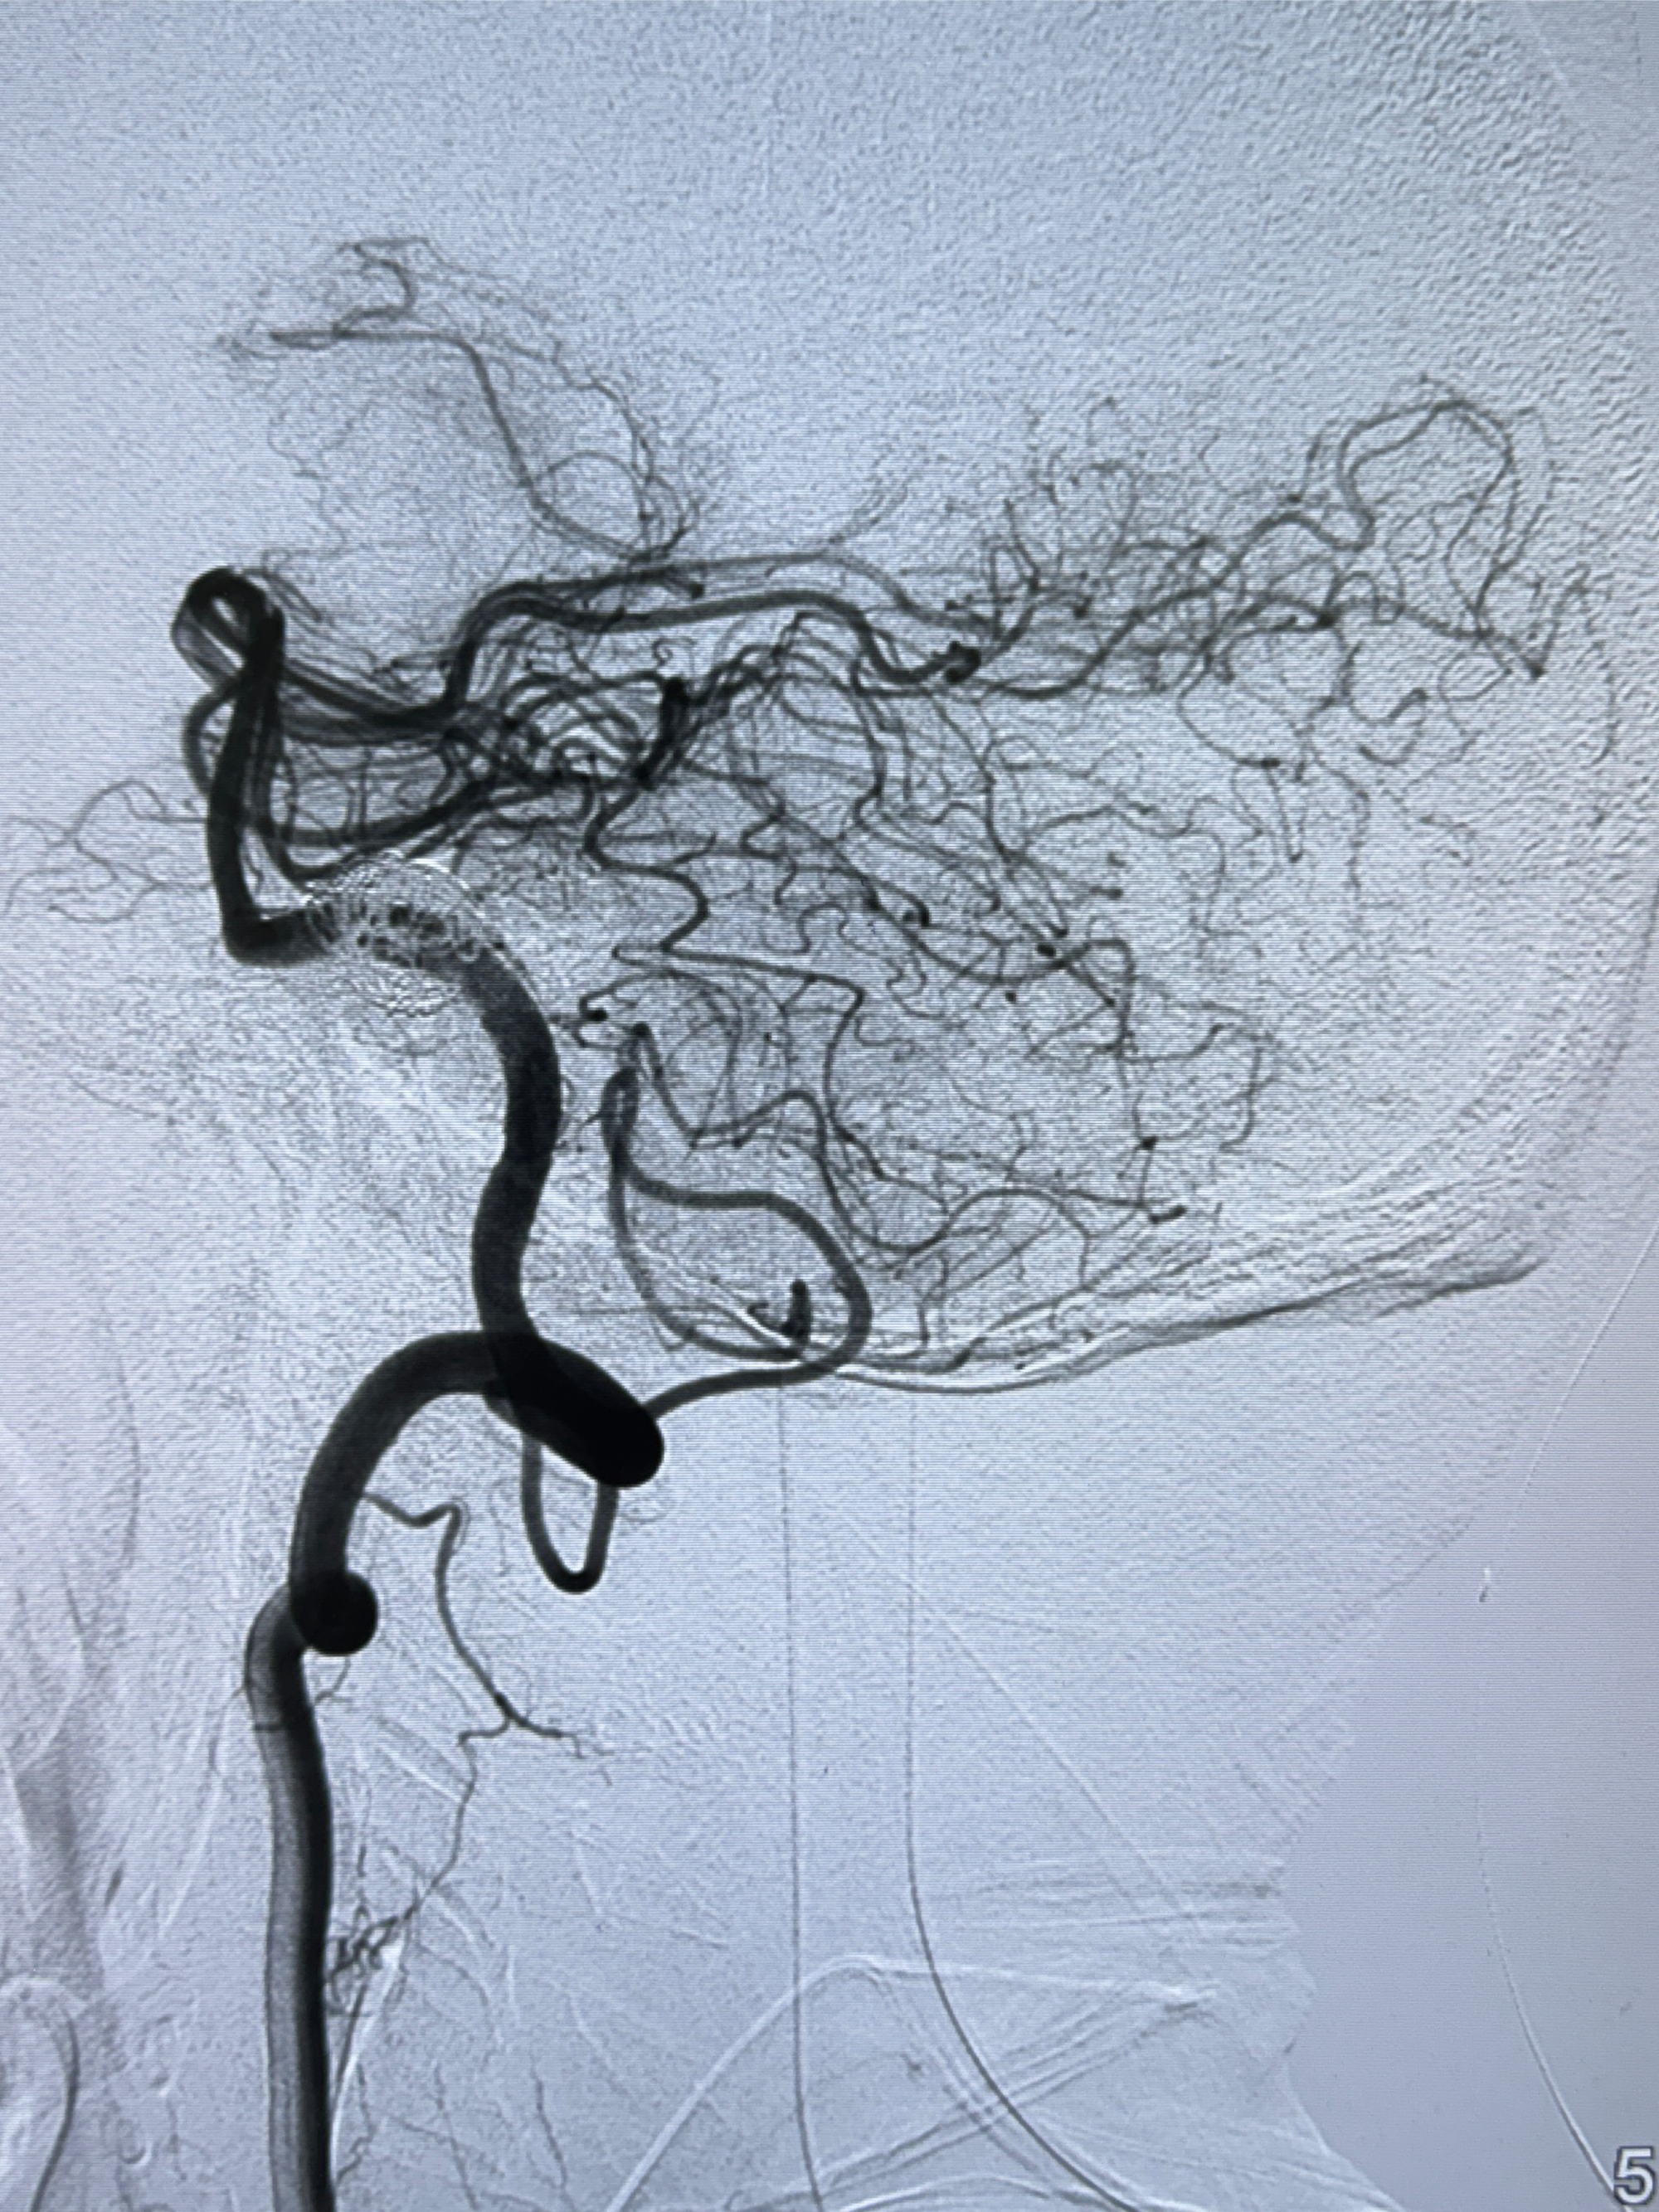

2024-01-08DSA:右侧椎动脉V4段夹层动脉瘤双支架辅助弹簧圈栓塞术后

患者支架辅助治疗后18个月,动脉瘤痊愈